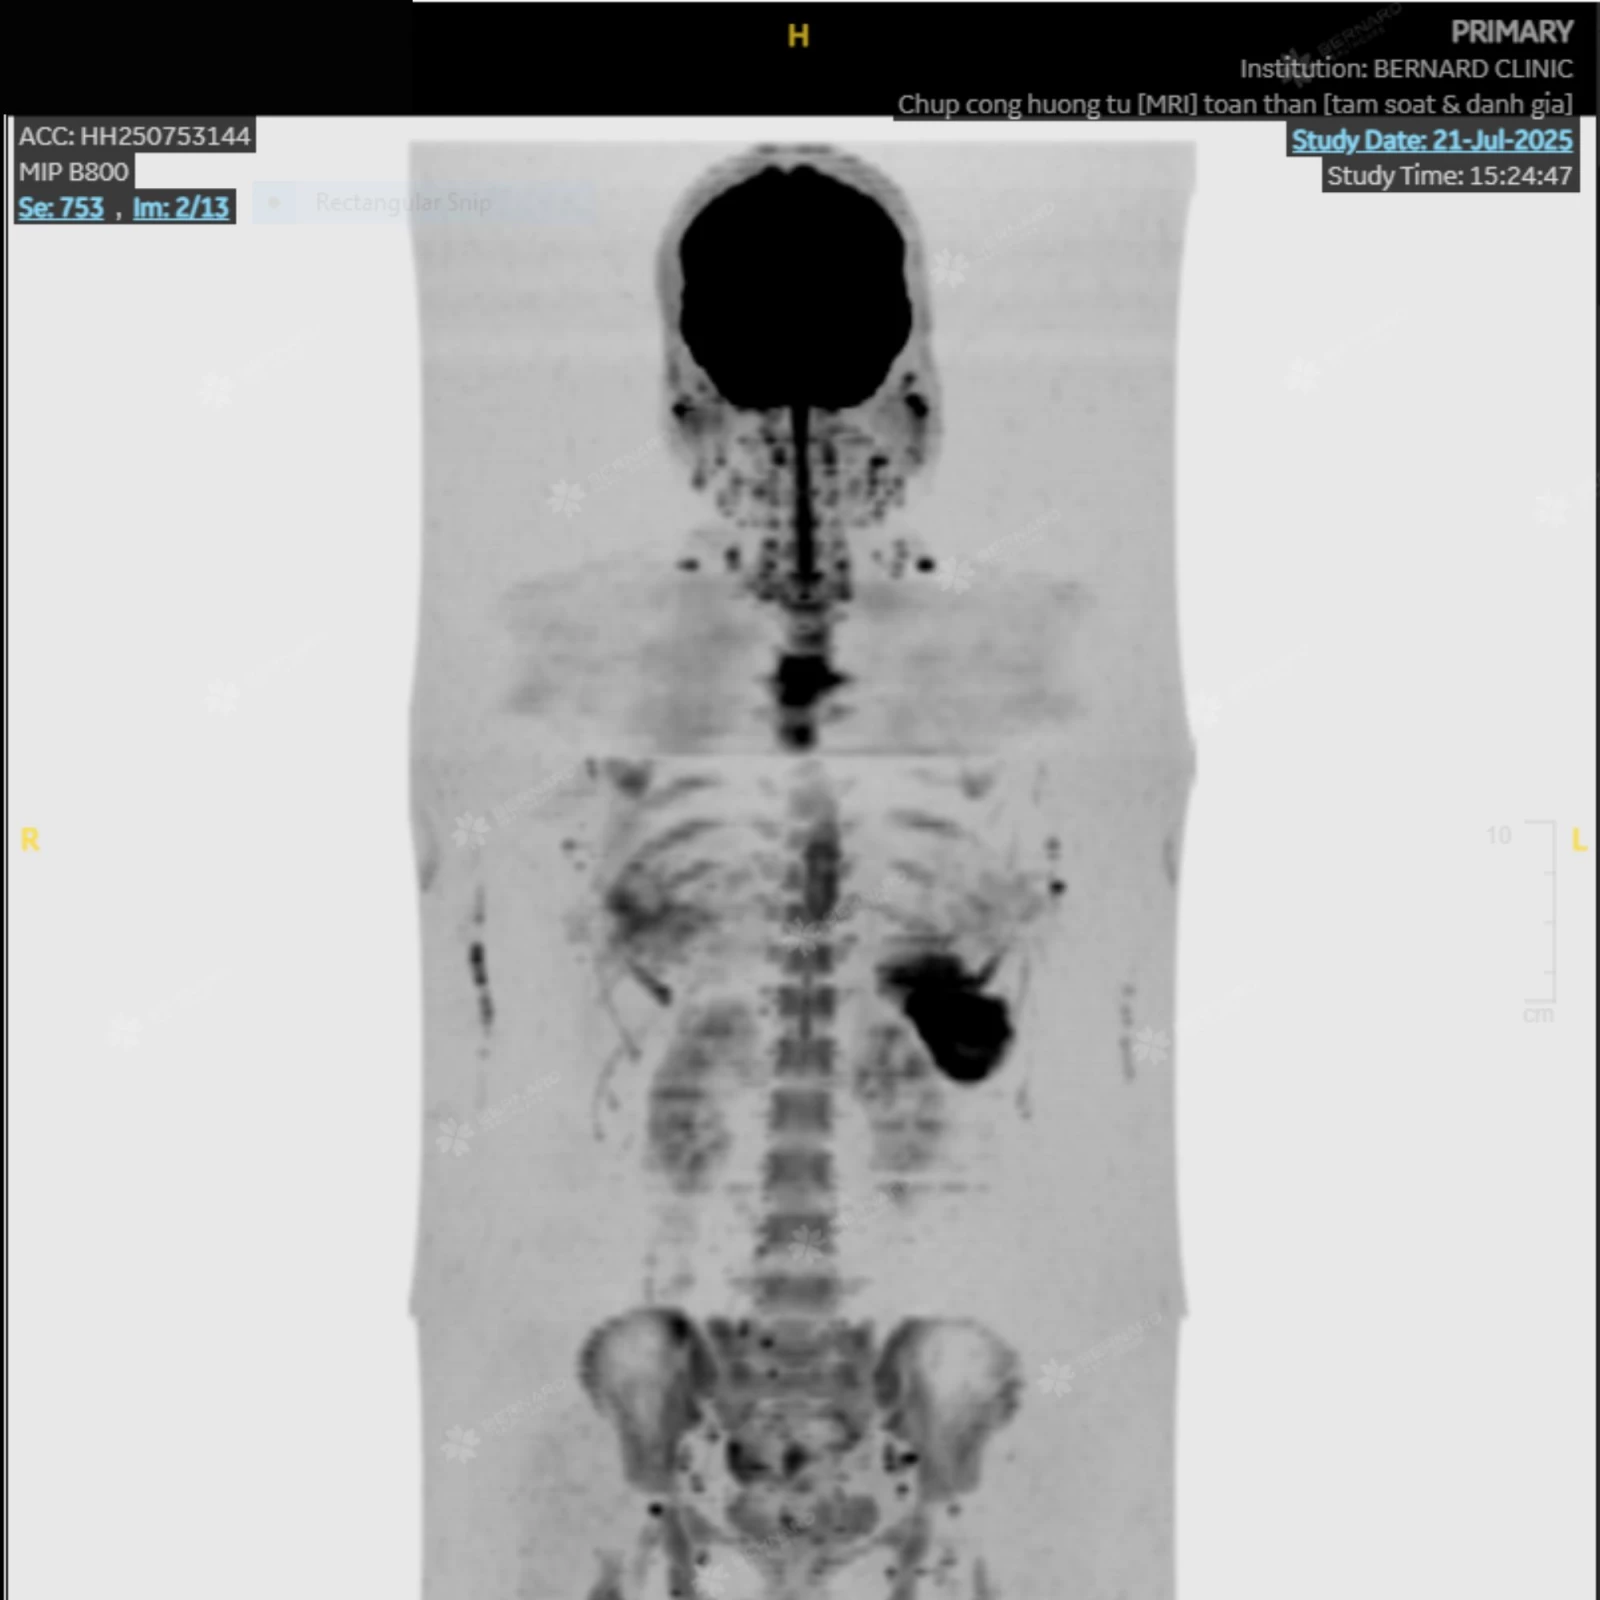

Kết quả MRI toàn thân ghi nhận những thay đổi bất thường ở vùng cột sống, xương sườn, xương chậu và đầu trên xương đùi hai bên, cùng tín hiệu bất thường ở vùng lách. Các dấu hiệu này gợi ý tình trạng tăng sản tủy xương (bone marrow hyperplasia).

Hình ảnh chụp MRI toàn thân của chị P. được trích xuất từ hệ thống PACS tại Bernard

Kết quả đọc chéo từ phía Bệnh viện Đại học Yamanashi đồng thuận với chẩn đoán gợi ý từ phía Bernard: Tăng sản tủy xương (bone marrow hyperplasia) và khuyến nghị kiểm tra chuyên sâu huyết học.